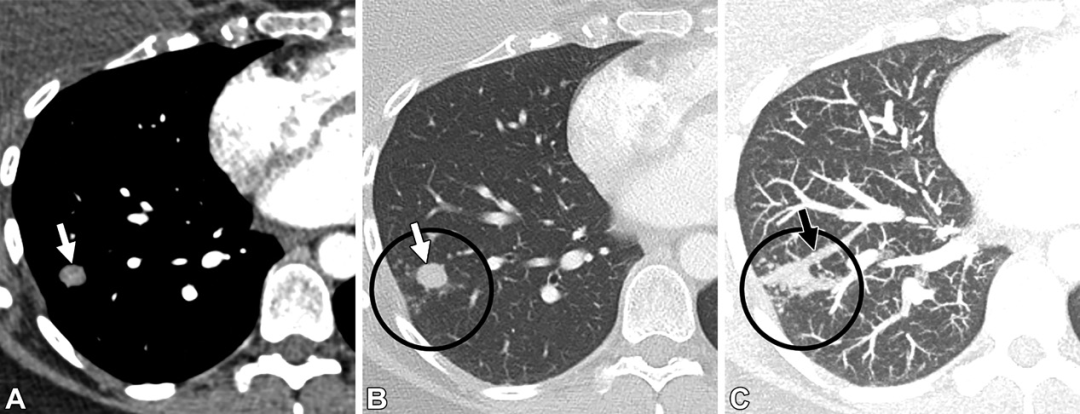

肉芽肿。36岁男性。轴位CT图,可见簇状结节(白色圆圈),中心呈高密度,外周可见小动脉(白色箭头)。以上表现最提示肉芽肿。后续基因检测及头颅磁共振均为阴性,患者也没有遗传性出血性毛细血管扩张症的家族史。

肉芽肿。31岁男性,有遗传性出血性毛细血管扩张症家族史。(A至C)轴位CT增强图,可见左肺下叶病变,伴供血动脉(白色箭头)以及中心高密度(白色星号),未见引流静脉。(D)随诊CT5年后,病变变小(白色星号),开始钙化。提示肉芽肿。

肉芽肿性病变。38岁女性。(A,B)轴位CT增强图,无强化的结节(白色箭头)伴多发邻近的卫星结节(黑色圆圈)。(C)轴位最大密度投影图,可见供血动脉(黑色箭头)及多发卫星结节(黑色圆圈),未见引流静脉或病灶。以上表现符合肉芽肿性病变。